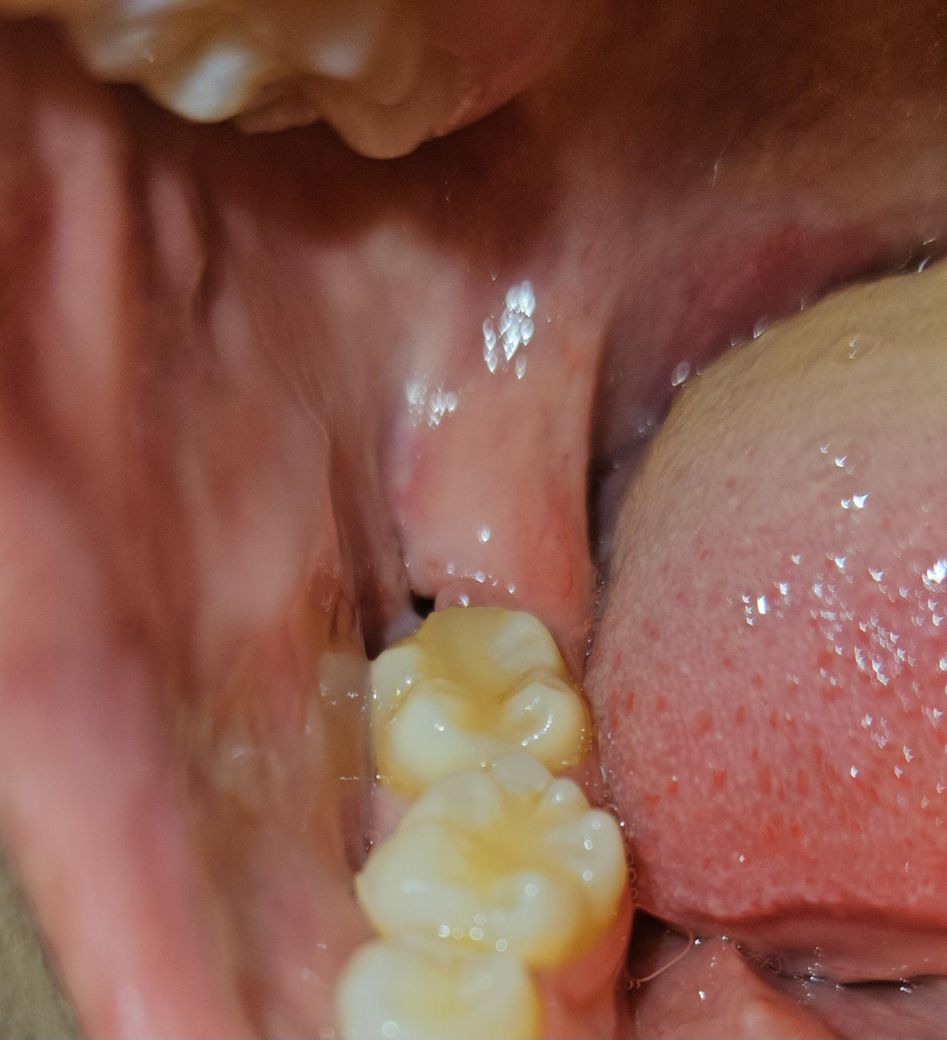

오늘 실밥 제거 했는데 입 벌려보니 무슨 시꺼먼게 보여서 봤는데.. 이게 도저히 구멍이 맞는지... 검정색 실로 꼬맷는데 저는 아무리봐도 실밥 같거든요?... 이게 구멍인가요?.. 너무 까만데... 진짜 뭐 붙어있는거처럼 까만데요... 반대쪽은 매복에 실밥 풀고 구멍이 없었거든요.. 원래 사랑니 뽑고 이렇게 구멍이 뻥 뚫리나요..ㅠㅠㅠㅠㅠ 실밥 제가하는것도 하나도 안아팠고요ㅠㅠ 진짜 몇초만에 끝났어요.. 실밥을 다 제거를 안해주신건가요?.. 과정이 그럴수가 있나요?... 제가 암만 후레시를 비춰봐도 모르겟어요....ㅠㅠㅠ 이거 아물면 어떻게 되는거죠..

• 1번 째 사진

사진에 보이는건 사랑니가 잇던 공간입니다. 시간이 지나면 잇몸이 아물면서 괜찮아 지니 너무 걱정하지마세요.

사진으로 봤을 경우에는 사랑니를 발치한 부위 내부에 구멍이 있는 것으로 보입니다.

사랑니가 크거나 매복되어 있는 사랑의 경우에는 발치한 부위에 구멍이 커 보일 수 있습니다. 이런 부위는 점차 시간이 지나면서 아물게 되면 보통 3개월 정도가 걸리게 됩니다.

실밥 아니고 구멍 맞을 것 같습니다 실밥 풀고도 구멍이 좀 있을 순 있습니다 걱정안하셔도 됩니다